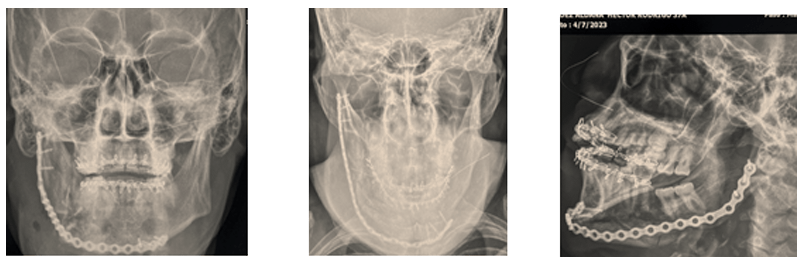

Imagen 5. Controles radiográficos postoperatorios.

A.) Proyección posteroanterior, B.) proyección Towne, C.) proyección oblicua derecha

Se citó nuevamente en un mes y una semana para reevaluación, evidentemente el edema había disminuido, la apertura bucal se encontraba normal, aproximadamente 45 mm, la oclusión dental en máxima intercuspidación y no había signos de proceso infeccioso alguno. En esa cita mediante anestesia local se retiraron arcos de Erich. El paciente ya podía reincorporarse a sus actividades diarias.

Se citó nuevamente 4 meses después de la operación y al encontrarse evolucionando satisfactoriamente se le dio caso concluido.